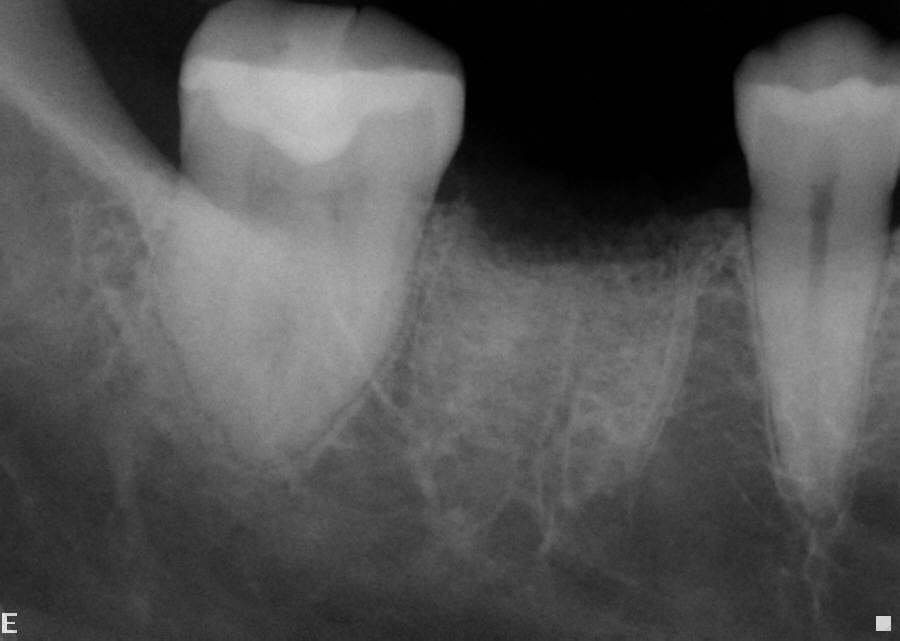

11. The grafted socket and soft tissue is allowed to heal and mature for a minimum of 6 weeks when the final treatment plan involves traditional fixed prosthodontics and a minimum of 4 months when considering implant placement (Figure 11).

Fig 11. Radiograph of a socket graft after placement.

Figure 11